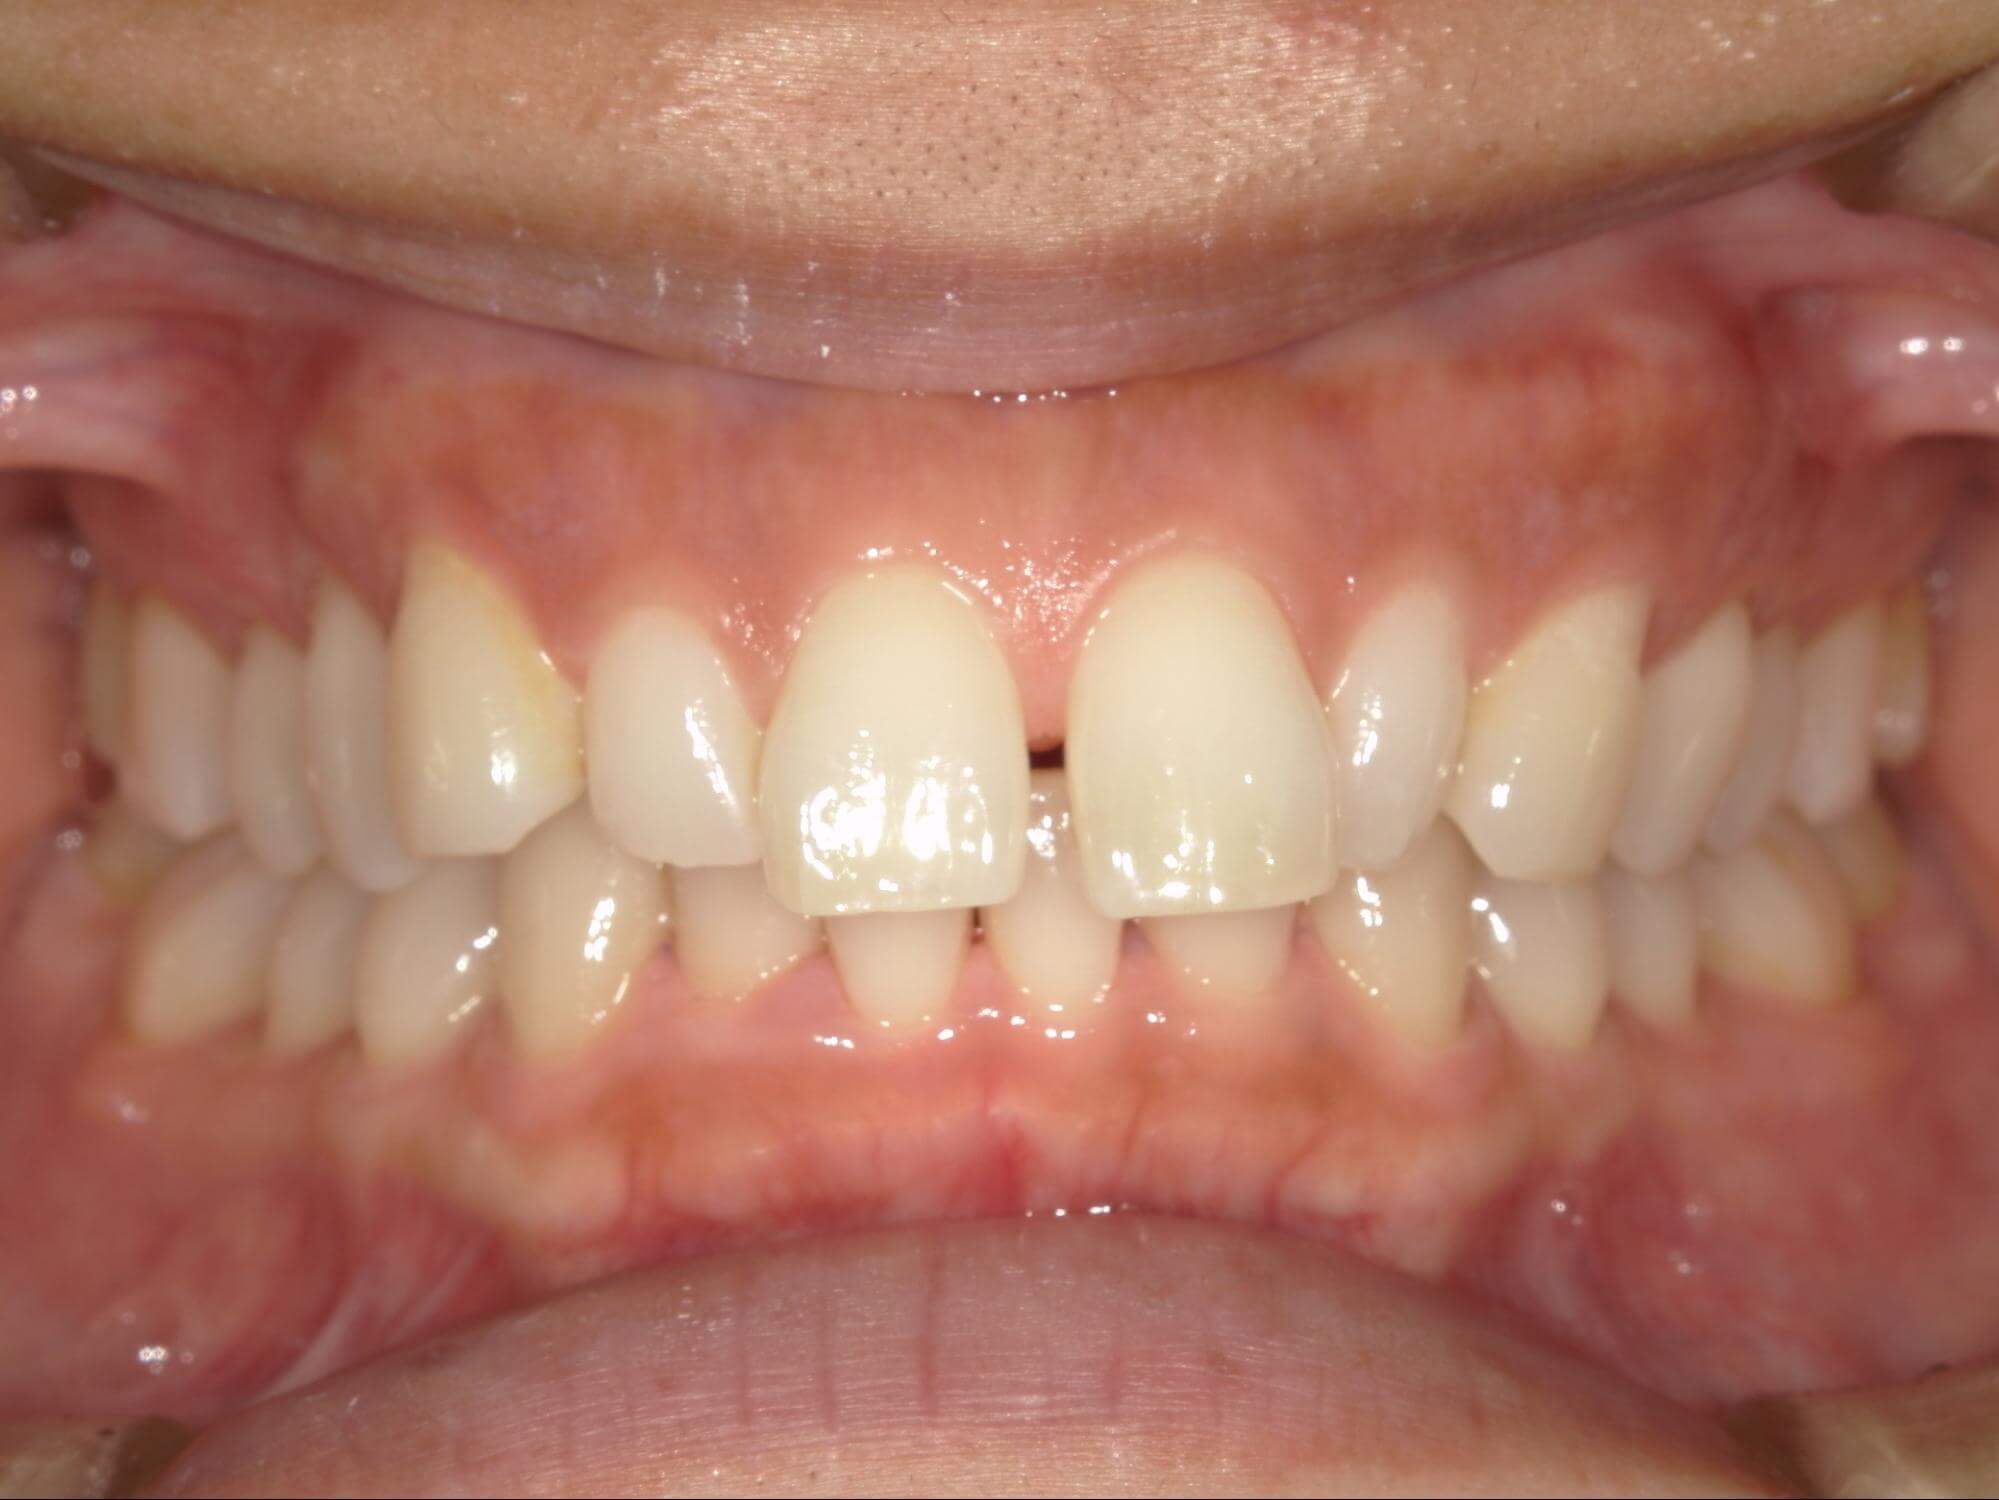

| 年齢・性別 | – |

|---|---|

| 主訴 | 叢生が気になる |

| 治療期間・回数 | 2年 |

| 費用 | 935,000円 |